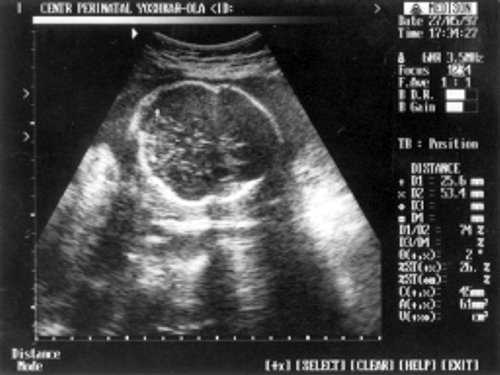

Данные фетометрии:

- (бипатериальный размер головы - от виска до виска) = 65 мм - 26 нед.,

- ОкГ (окружность головы) = 244 - 26 нед. + 3 дня.

- МРМ (межполушарный размер мозжечка) = 25,6 мм - 23,5-24 нед. (рис. 1)

- ОкГрК (окружность грудной клетки) = 42 мм - 19,5 нед.

- ОЖ (окружность живота) = 182 мм - 22 нед. + 6 дн.

- ДБ (длина бедра) = 24 мм - 17 нед. (рис. 2)

Рис. 1. УЗИ плода - голова.